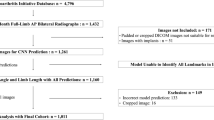

A retrospective study was conducted using previously collected WBCT scans of patients with unilateral syndesmotic instability. One-hundred and forty-four bilateral ankle WBCT scans were evaluated (48 unstable, 96 control). We developed three deep learning models for analyzing WBCT scans to recognize syndesmosis instability. These three models included two state-of-the-art models (Model 1—3D Convolutional Neural Network [CNN], and Model 2—CNN with long short-term memory [LSTM]), and a new model (Model 3—differential CNN LSTM) that we introduced in this study.